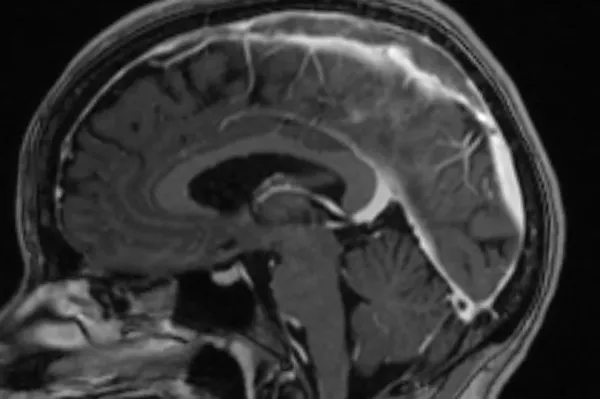

Brain tumours are currently the biggest cancer killers of children and adults under 40 in the UK, according to the Brain Tumour Charity. Around 13,000 people are diagnosed each year with a primary brain tumour, including 900 children and young people.